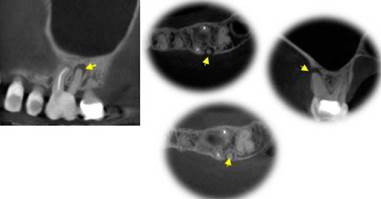

Las (figuras 10-14), corresponden a un caso clínico que demuestra la retropre-paración e irrigación del tercio apical en micro-cirugía endodóntica, como pasos fundamentales para un resultado éxitoso del tratamiento. Es importante tener encuenta que las variaciones anatómicas presentes en el sistema de conductos pueden dejar algunos conductos sin tratamiento endodóntico y por lo tanto contribuyen al fracaso 51, donde casi 91% de los conductos omitidos se asociaron con lesion periapical 52.

Figura 10 CBCT del diente 26 en los planos sagital, axial y coronal, mostrando conducto omitido en el tratamiento endodóntico previo, el cual es causa de la lesión periapical encontrada. Cortesía del Doctor Rafael fernández